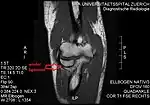

T1 weighted MRI showing the anular ligament